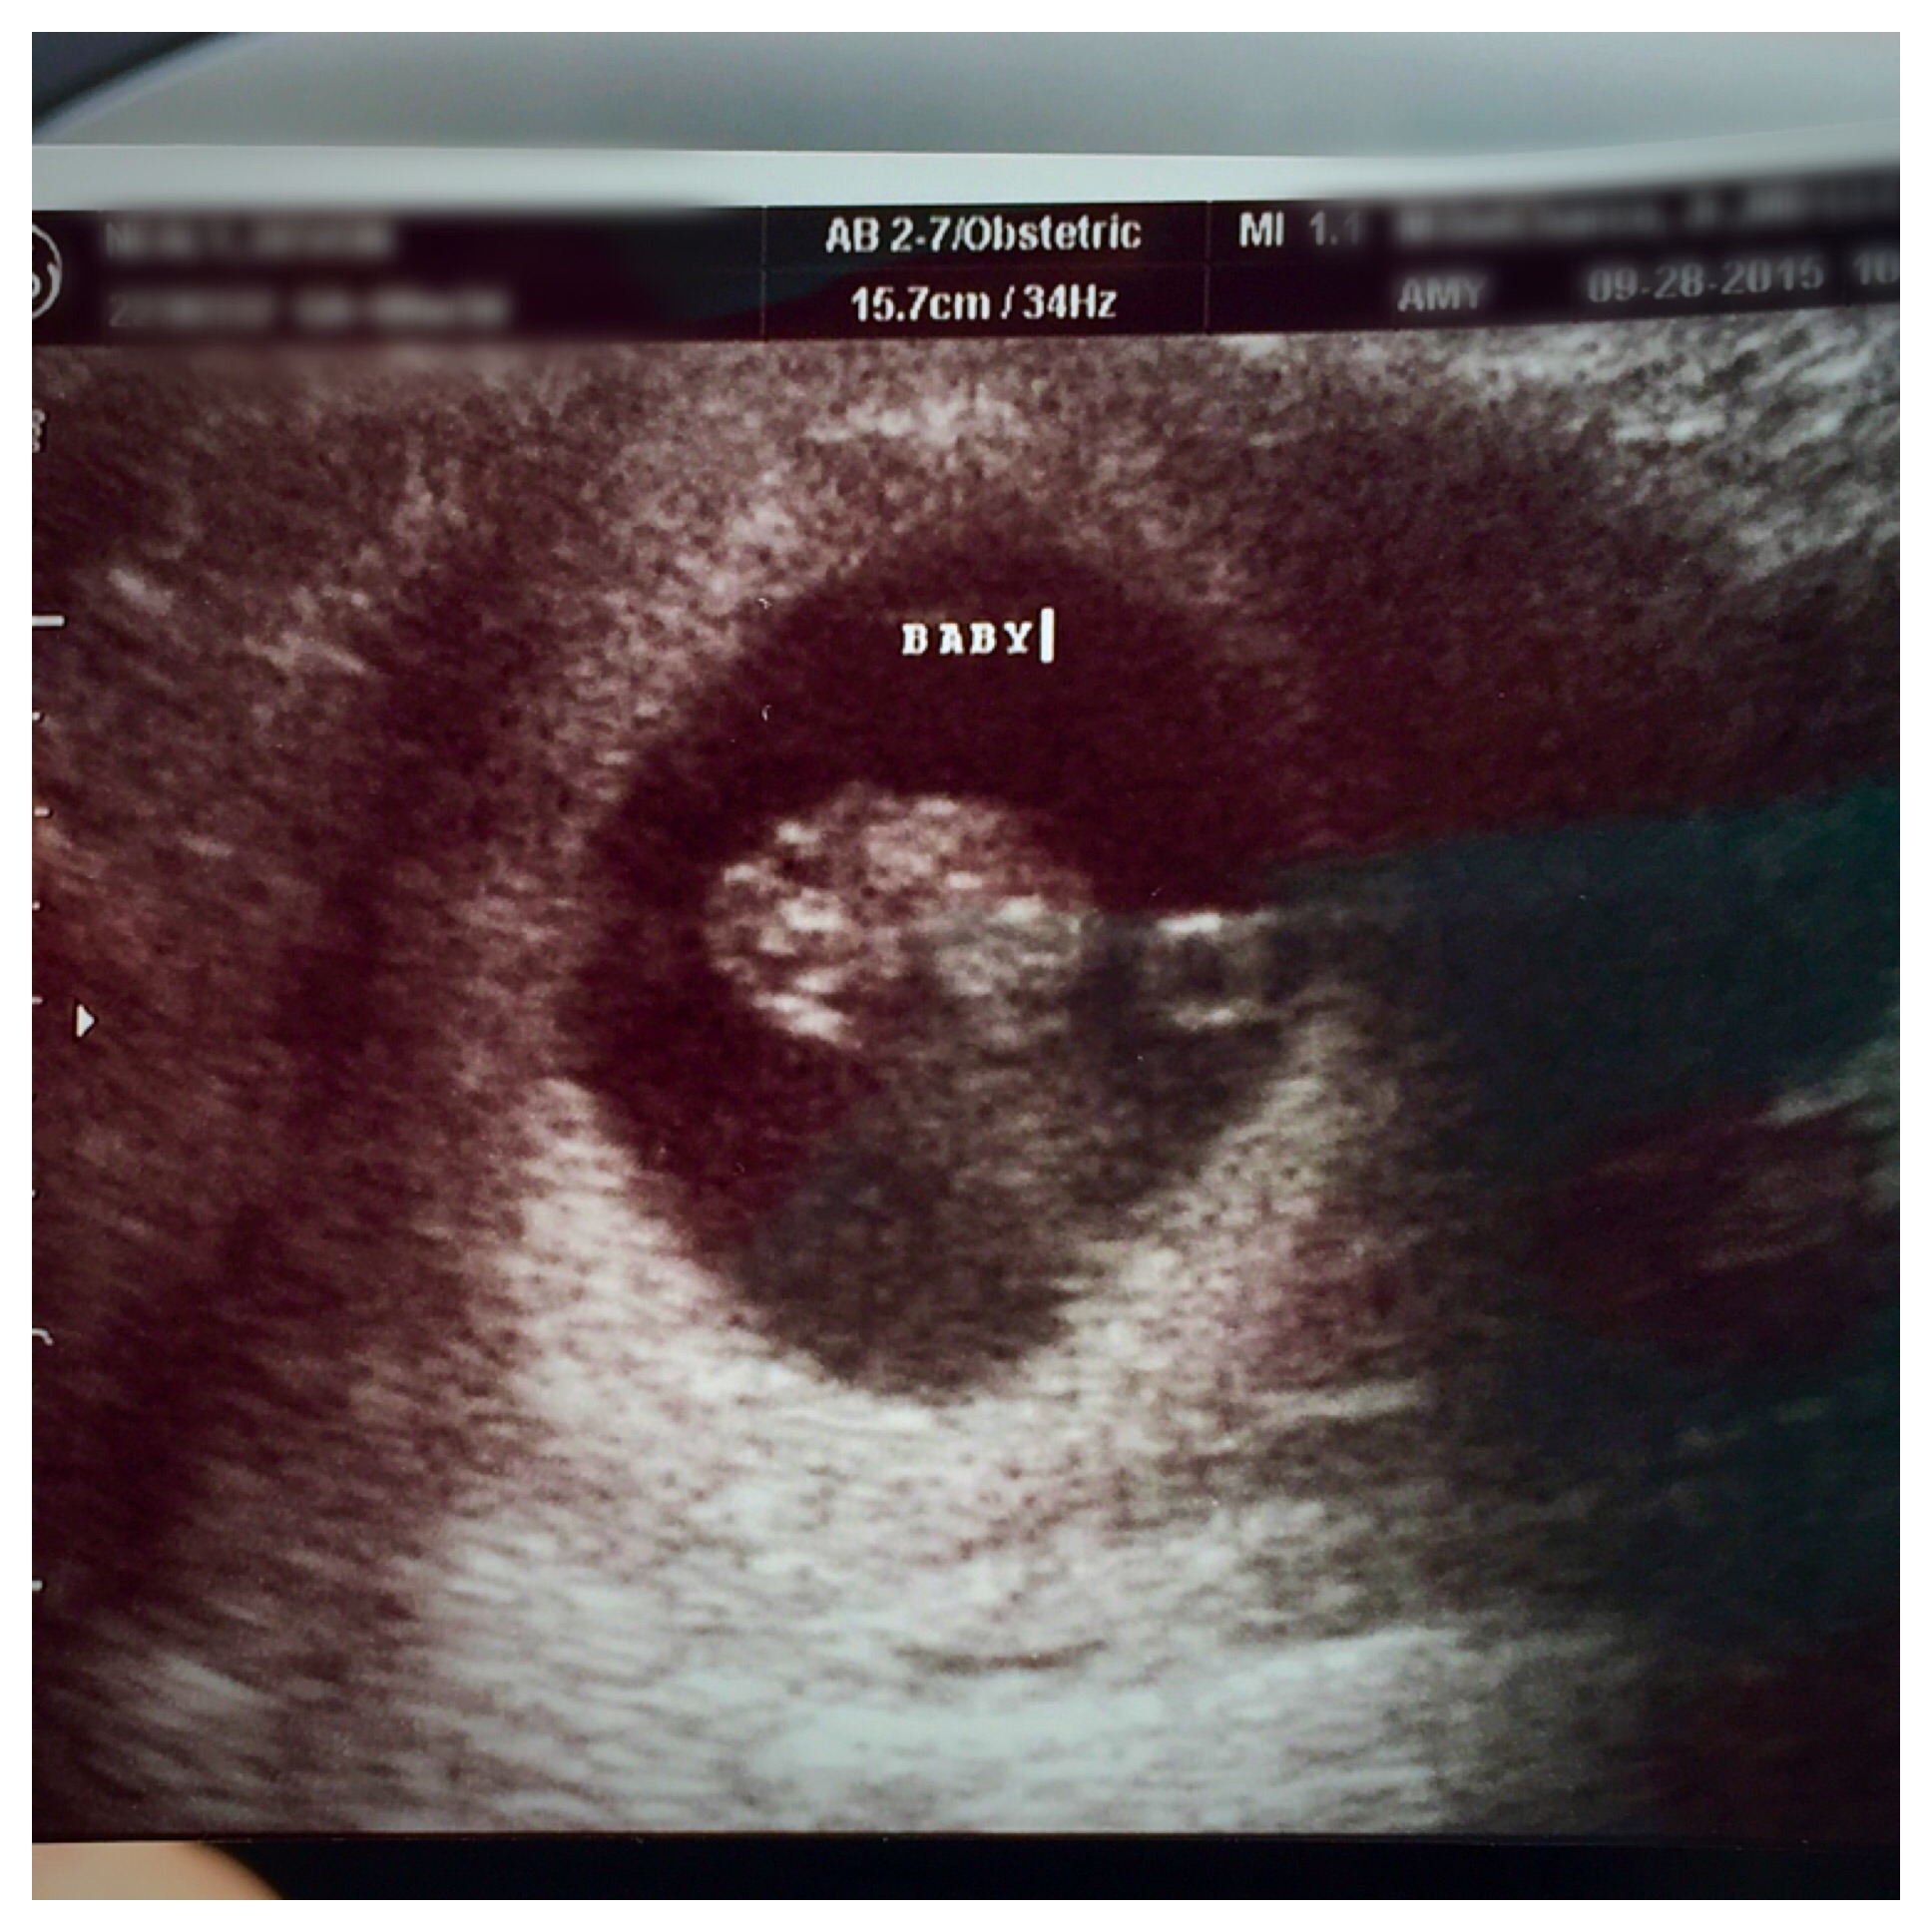

We had our first appointment today and saw LO! I'm 9 weeks today, baby looks great and has a strong heartbeat (169 bps). Seeing that little heartbeat always makes me cry.